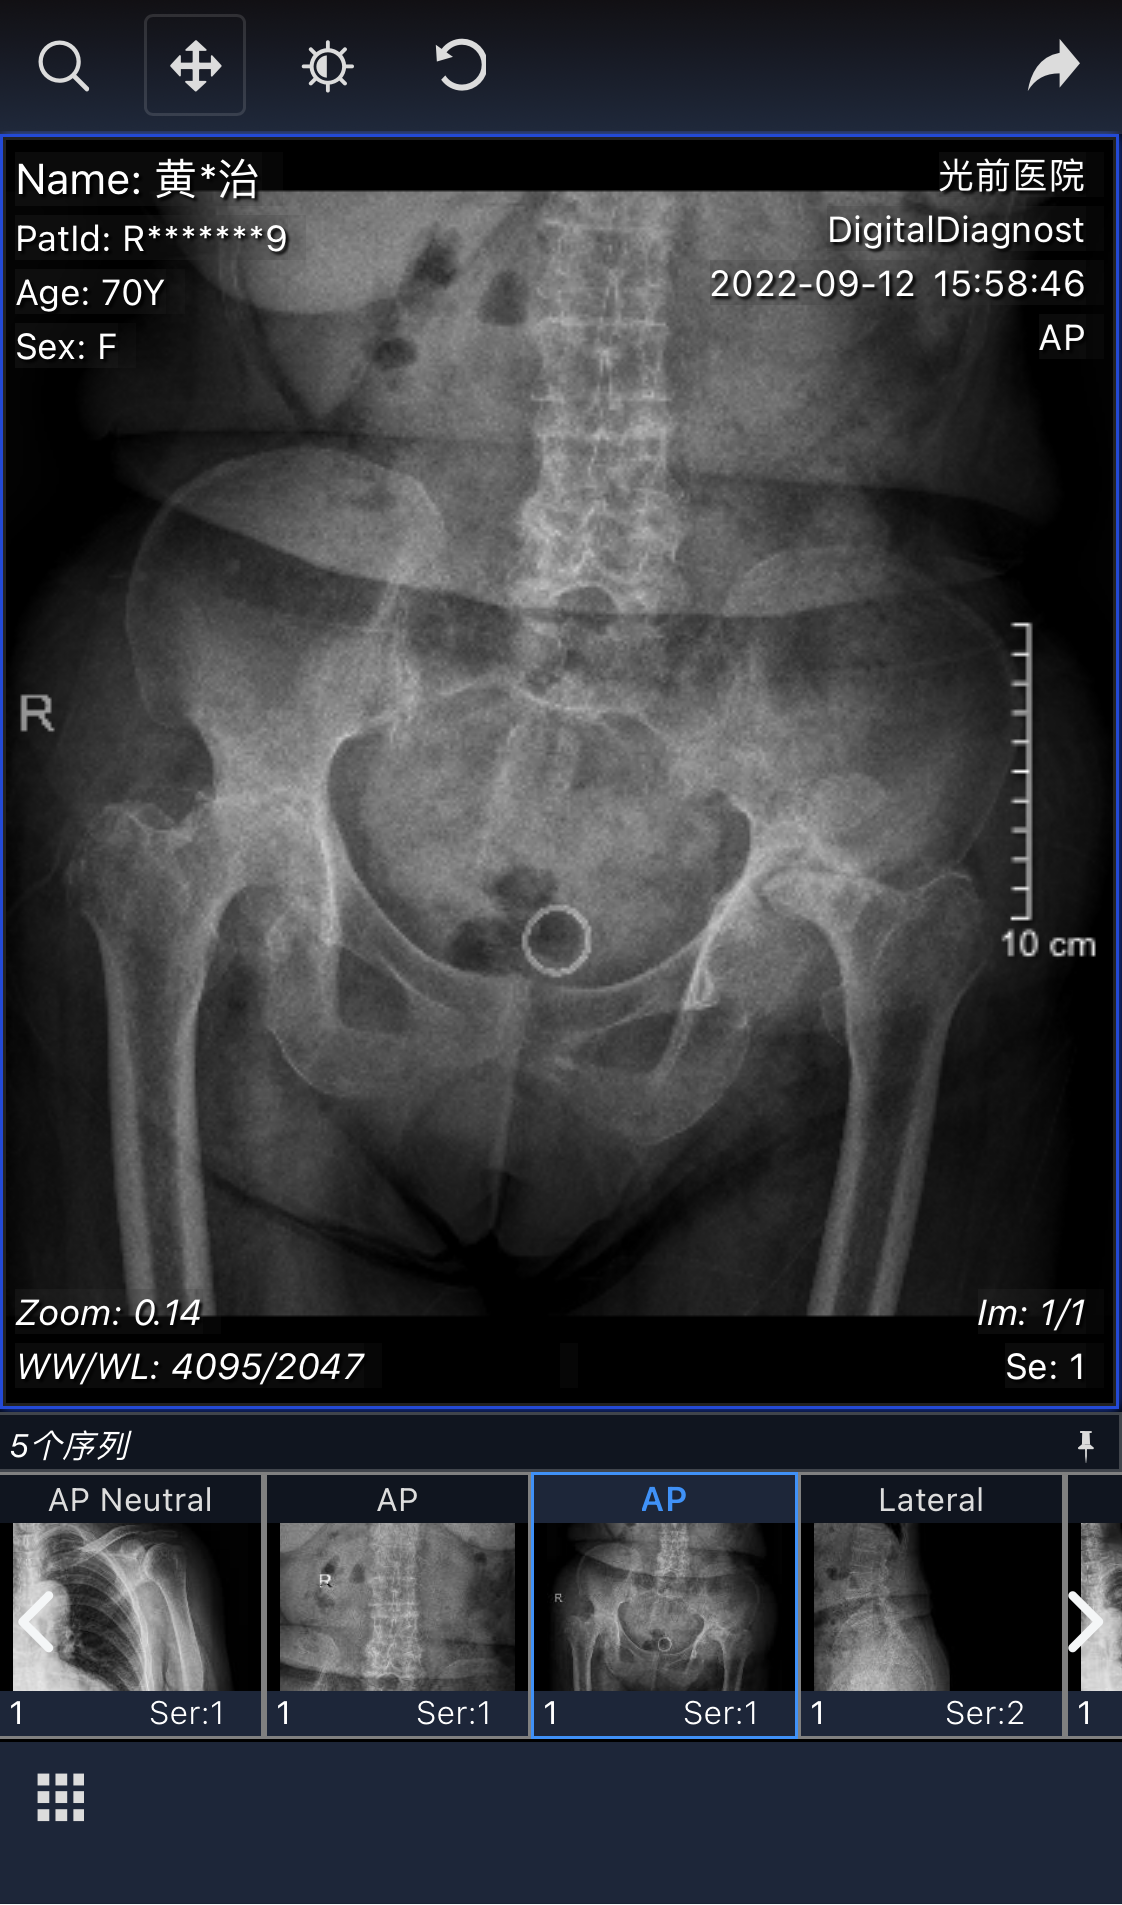

黃阿婆是南安梅山一名地地道道的農(nóng)民,患有類風(fēng)濕關(guān)節(jié)炎,長(zhǎng)期口服藥物治療。10年前身體開始疼痛到難以忍受,甚至夜間出現(xiàn)疼痛得難于入眠的情況,走路也劇痛難忍,出行只能依靠拐杖和輪椅。由于家境貧困,舍不得花錢到醫(yī)院進(jìn)行正規(guī)治療,導(dǎo)致病情不斷加重,出現(xiàn)雙側(cè)股骨頭壞死,嚴(yán)重影響了日常生活。最后不得已只能到各處求醫(yī),卻都因被告知手術(shù)風(fēng)險(xiǎn)大、手術(shù)費(fèi)用高后而退卻了。

就在去年,黃阿婆一家聽說家門口的泉州市光前醫(yī)院關(guān)節(jié)置換技術(shù)過硬,費(fèi)用報(bào)銷比例高,決定試一試。接診的骨科主任黃進(jìn)福主任醫(yī)師在仔細(xì)閱片及查體后,告知手術(shù)成功率高,報(bào)銷完僅需自費(fèi)幾千元,術(shù)后即可恢復(fù)正常行走。黃阿婆及家屬聽聞后,喜出望外,決定在光前院進(jìn)行手術(shù)治療。

手術(shù)前后對(duì)比